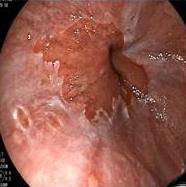

• 经皮经胆道镜激光消融术与光动力疗法治疗胆管黏液性囊性肿瘤的临床疗效及治疗技巧

2026, 32(1):84-88. DOI: 10.12235/E20250025

摘要:目的 探讨经皮经胆道镜激光消融术与光动力疗法(PDT)治疗胆管黏液性囊性肿瘤的临床疗效及治疗技巧。方法 回顾性分析2018年1月-2023年12月该院消化内科收治的13例胆管黏液性囊性肿瘤患者的临床资料,采取经皮经胆道镜激光消融术、PDT治疗或两者联合治疗。观察患者手术相关情况、病灶情况、引流情况、术后6个月生存情况和并发症发生情况。结果 所有患者均顺利完成经皮经胆道镜激光消融、PDT或两者联合治疗,治疗成功率为100%。所有患者术后体温恢复正常。7例患者术后1周内黄疸明显减退,其余6例黄疸虽然未明显减退,但血清总胆红素有所下降或保持稳定。所有患者术后1周内,胆管各分支新生物减少,病灶明显缩小。术后早期(30 d内),所有患者引流管均保持通畅,未发生因肿瘤组织脱落或坏死物堵塞所导致的急性堵管事件。术后引流管留置时间平均为4.2个月。术后6个月,无死亡病例,术后6个月生存率为100%。未发生胆道穿孔和大出血等严重并发症。结论 经皮经胆道镜激光消融术联合PDT治疗胆管黏液性囊性肿瘤,可以缩小病灶范围,缓解胆道梗阻,提高患者生活质量,且并发症少。值得临床推广应用。